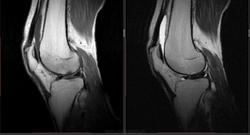

Мужчина 1963 г.р. Жалуется на боль в левом коленном суставе около 6 мес, в последний месяц стало совсем тяжко. Со слов заболел зимой, когда во время прогулки коленки сильно замерзли. Сам думаю на асептический некроз, но смущает множественность поражения.

Дмитрий, я в заболеваниях суставов не дока, но трабекулярный отек вкупе с выпотом может быть обусловлен воспалительными изменениями , но полностью начальные проявления аваскулярного некроза не могу отрицать.

я бы не поставил аваскулярный некроз. если исключена травма, дифференцировать с артритом.

Хрящ не поврежден, для артрита...